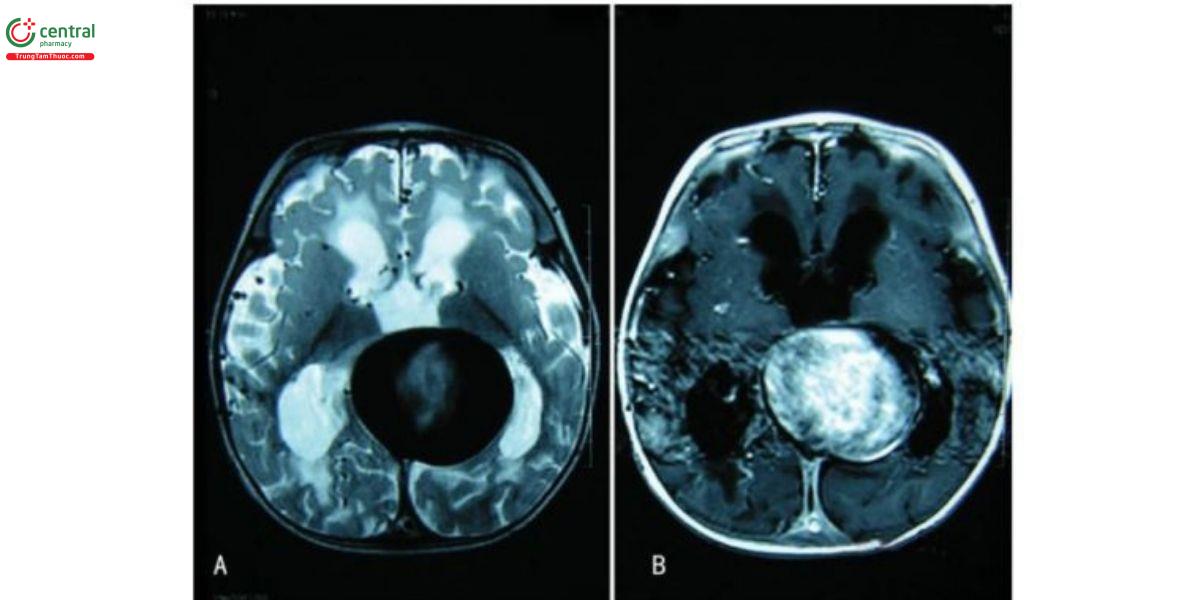

Sự dẫn lưu của dị dạng hướng về xoang thẳng, và cũng có thể dẫn lưu vào xoang dọc trên thông qua xoang liểm tổn tại, trong trường hợp này, xoang thắng sẽ bị thiểu, kém phát triển hoặc hẹp. Các trường hợp VGAM có xoang liềm tồn tại đã từng được chúng tôi bảo cáo trước đây (Hình 2). Dị dạng động tĩnh mạch được cấp máu bởi nhiều mạch nuôi khác nhau, bao gồm mạng dưới màng ổng nội tủy có nguồn gốc từ vòng Willis phía sau, các động mạch xuyên đổi thị, các động mạch mạch mạc, và cung động mạch hệ viền. Dị dạng này nằm trong bể velum interpositum cũng như bể củ não, và theo quan niệm truyền thống, không có kết nối giữa dị dạng và hệ tĩnh mạch sâu. Tuy nhiên, lý thuyết này đã bị thách thức trong các báo cáo gần đây. Trong các nghiên cứu này, sự dẫn lưu của dị dạng vào hệ tĩnh mạch sâu đã được xác nhận bằng hình ảnh theo dõi, bao gồm tĩnh mạch não trong, xoang thăng, xoang liểm, tĩnh mạch đáy Rosenthal và xoang dọc dưới.

Huyết khối tự phát trong VGAM là hiểm và cơ chế vẫn chưa được hiểu đầy đủ. Có nhiều yếu tố được mô tả, bao gồm thay đổi huyết động (dòng chảy chậm, tăng áp lực hoặc nhiều loạn), co mạch, tăng sinh mạch, và các thay đổi xơ vữa thoái triển trong mạch máu. Dẫn lưu thất và việc sử dụng thuốc cản quang trong chụp mạch cũng được cho là có liên quan đến huyết khối trong VGAM. Các phương pháp hình ảnh có thể mô tả rõ các đặc điểm của huyết khối. Trên CT, có thể thấy tin hiệu không đồng nhất, đôi khi kèm theo vôi hóa. CT cản quang cho thấy huyết khối trung tâm và dòng máu tuần hoàn quanh thành túi, được gọi là "target sign", MRI của VGAM có huyết khối cho thấy methemoglobin ngoại bào ở phần trung tâm và hemosiderin ở phần ngoại vi của tôn thương.